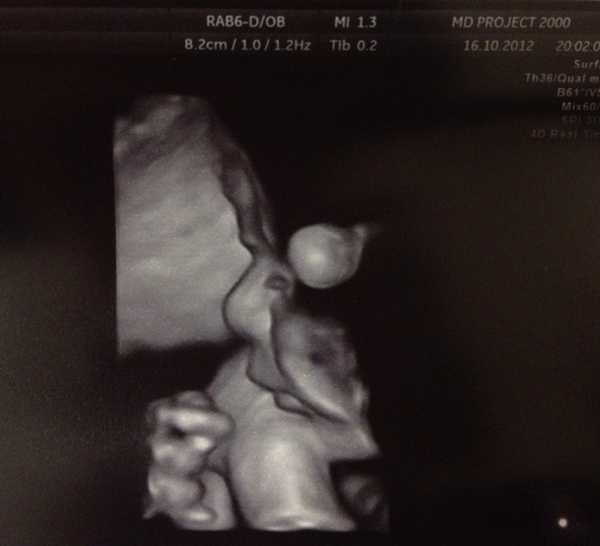

В ту ночь я попросила всех своих знакомых помолиться за меня, а наутро побежала сдавать кровь на ХГЧ, чтобы знать точку отсчета и убедиться в том, что беременность развивается. Решение уже было принято. Далее следовало УЗИ в 7 недель, где мне показали бьющееся сердечко малыша, еженедельные замеры уровня ХГЧ для снижения паники и ежевечерние мольбы к Всевышнему о помощи и разговоры с самой собой о принятии уготовленной мне судьбы.